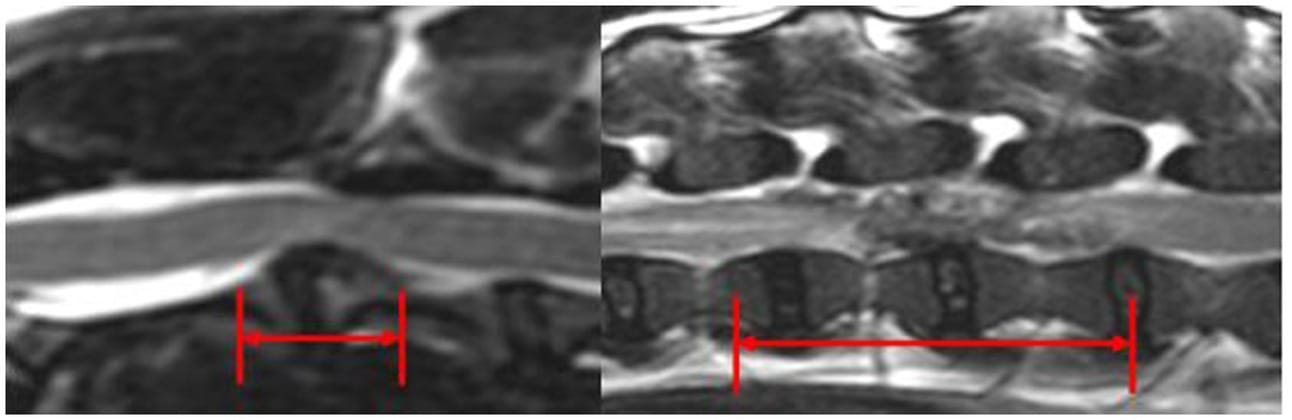

Mid-sagittal T2w images at the level of C2-C3 IVD (left) and L2-L3 IVD (right). The red arrows evaluate the longitudinal extent of the EIVDM within the vertebral canal.